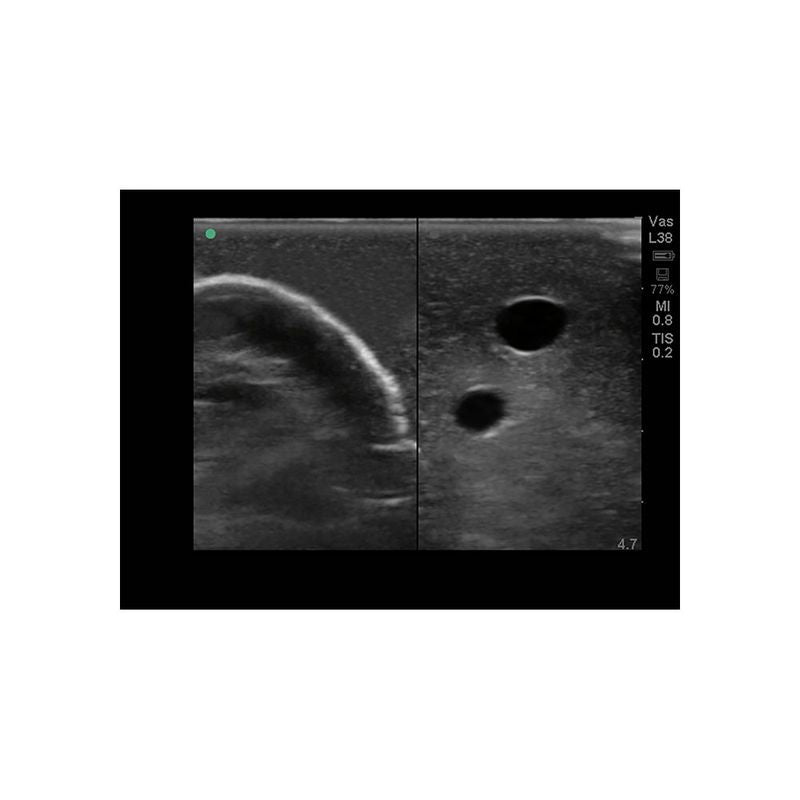

Replacement tissue insert for Central Line and Regional Anesthesia Model (BPHNB670 series).-